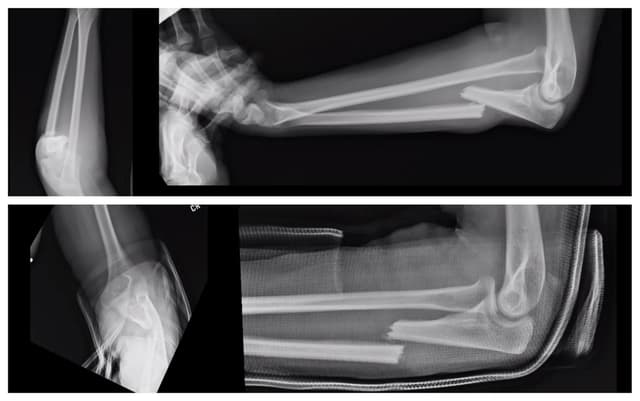

Imaging

Pre-op